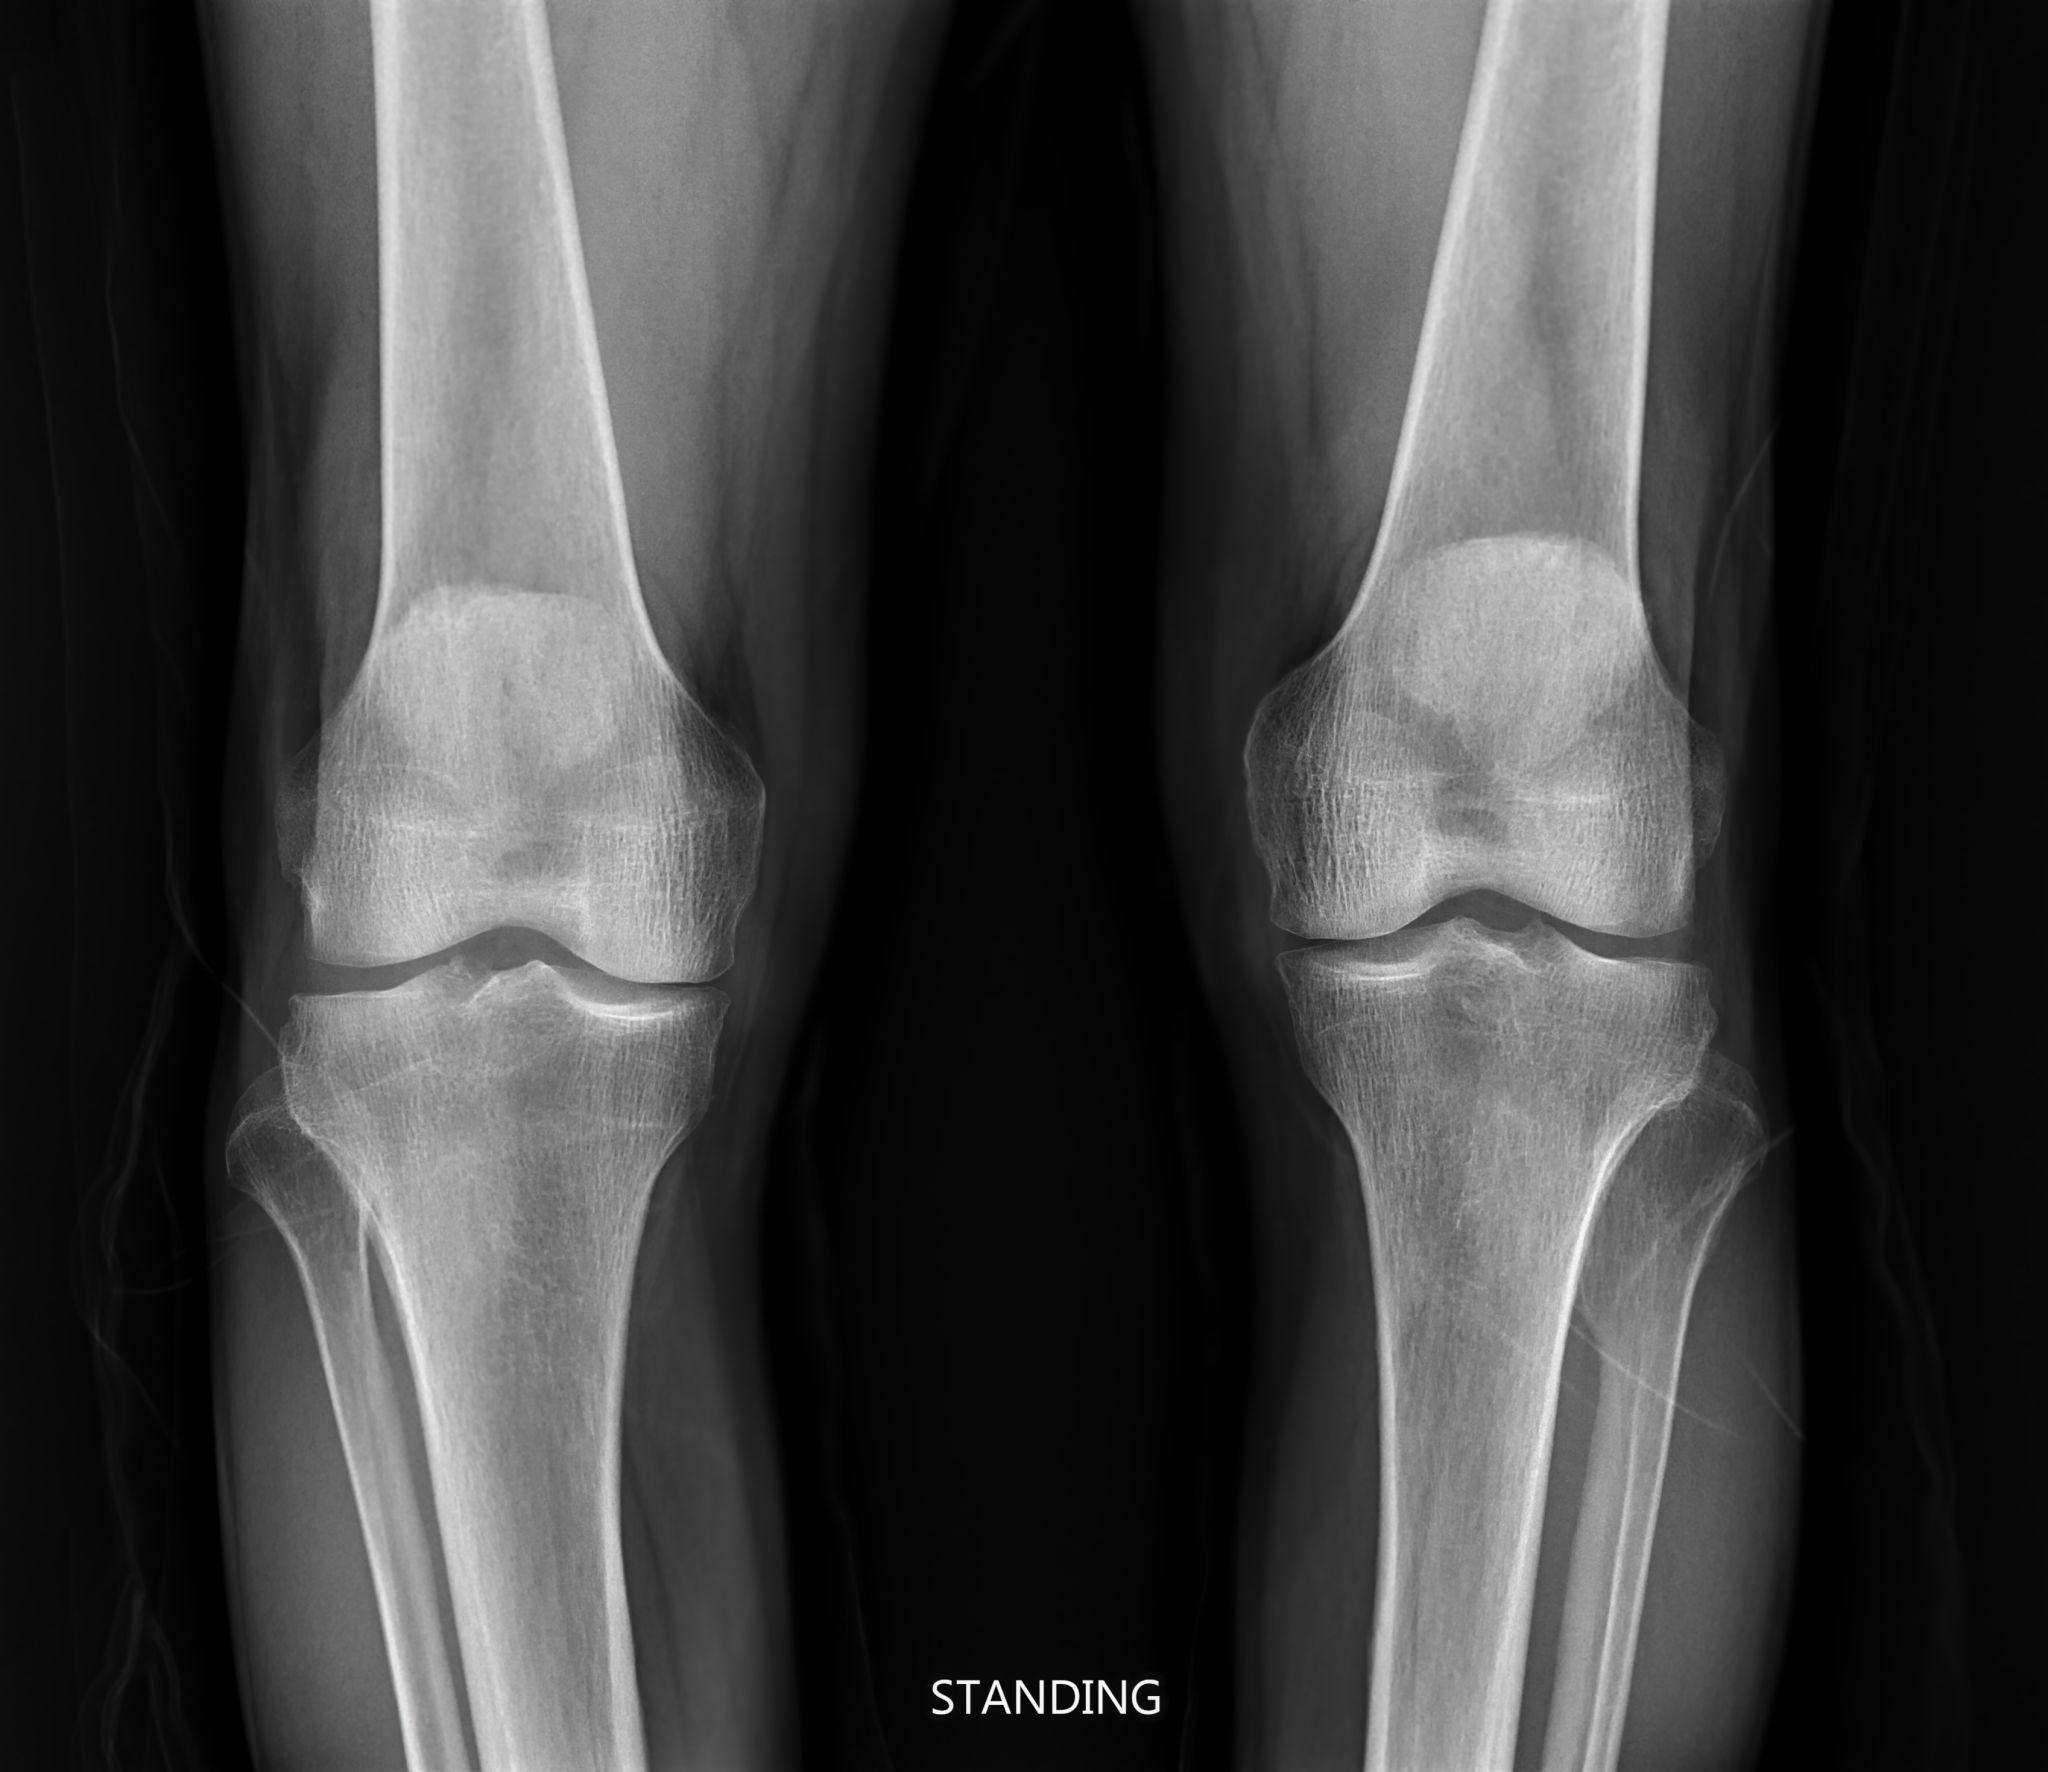

Dolore al ginocchio? Le radiografie giuste fanno la differenza.

Dolore al ginocchio o all’anca?Ecco come capire se l’artrosi è in fase avanzata.

Sostituzione totale o parziale (monocompartimentale) del ginocchio in pazienti con artrosi avanzata. In casi selezionati utilizza anche chirurgia robotica per migliorare la precisione dell’impianto.

Per pazienti non chirurgici: infiltrazioni articolari, artroscopia e prime valutazioni in fase iniziale. Se l’artrosi è di grado lieve-moderato propongo soluzioni meno invasive.